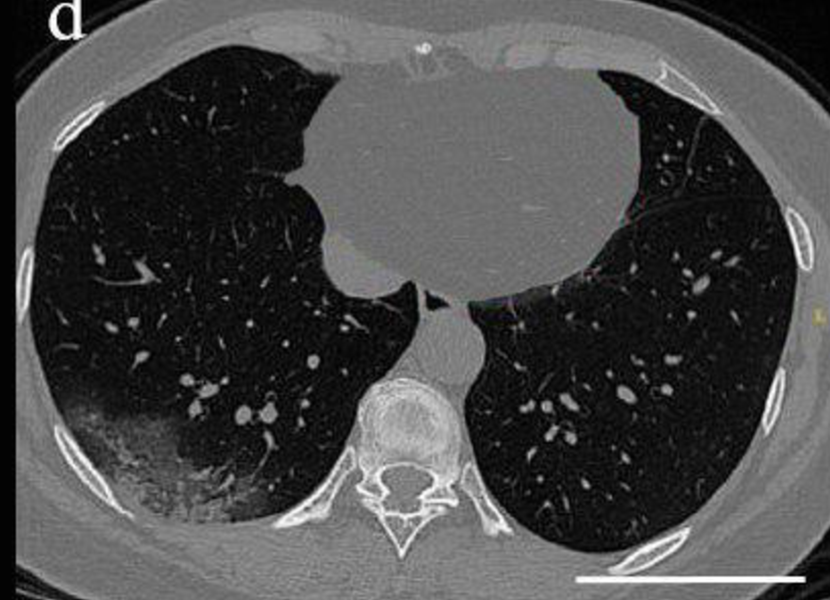

CT dataset has 349 Covid images and 397 non-Covid images [37]. Health professionals prefer breast CT scans as they carry more information compared to chest X-rays to use for medical diagnosis. Fig. 3 shows both a Covid and a non-Covid case from the CT database.

Figure 3: Two sample images from CT dataset.